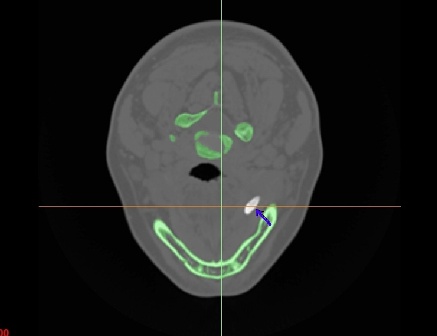

Камені у слинних залозах або їх протоках далеко не таке рідкісне захворювання як прийнято вважати (за статистикою їм страждає близько 1,3% усього населення). Для підтвердження цього діагнозу необхідне спеціальне обстеження (МРТ або комп’ютерна томографія). Основні симптоми слиннокам’яної хвороби

Стрілкою вказано стовбур лицевого нерва, який необхідно зберегти під час втручання